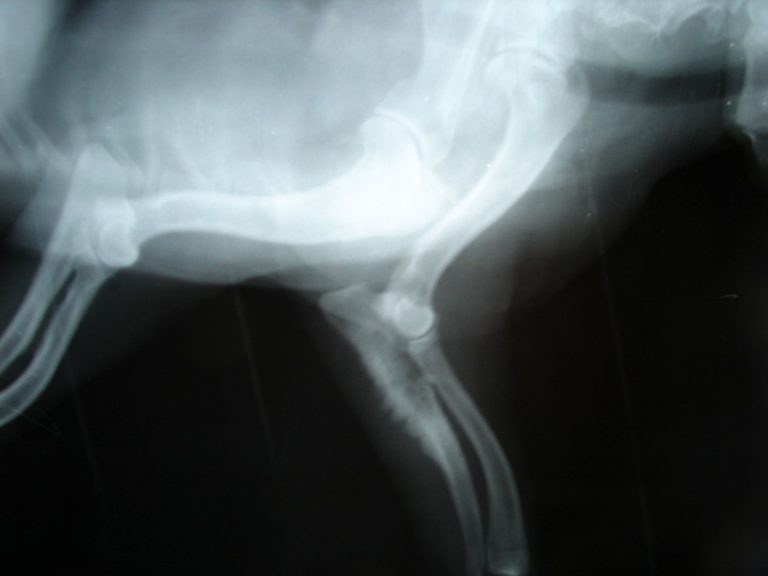

Så gör jag: Patricio Rivera: Cancervård kräver både förnuft och känsla

Möjligheterna att behandla tumörsjukdomar har utvecklats dramatiskt på senare år. Men för att hitta den rätta behandlingen krävs mycket stor nogrannhet. Det berättar klinikveterinären Patricio…